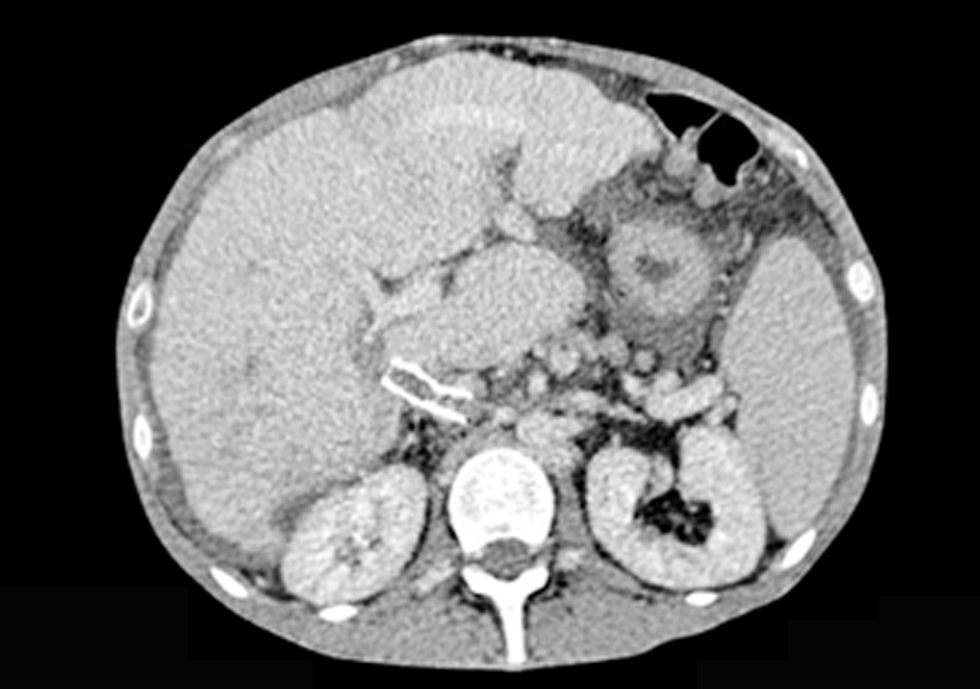

Our patient received continue theraphy with dabigratan etexilat (Pradaxa) 9 month and she performed CT scan every 3 month. In june 2018 CT scan evaluation described moderate ascities due to DIPS thrombosis (figs. 2, 3, 4).

Figure 3 - CT scan 1.5 mm coronal - Direct Intrahepatic Portocaval Shunt thrombosis (June 2018)